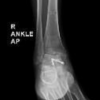

On examination, his right thumb and thenar eminence were grossly swollen, erythematous and exquisitely tender to palpation. He held the thumb in flexion, with the interphalangeal and metacarpophalangeal joint movements very limited and painful. There was a small superficial collection dorsally on the radial aspect of the proximal phalanx base. Ascending lymphangitis was present extending into the axilla but without palpable lymph nodes. Also noted was a small, nearly completely healed puncture wound at the fingertip. He recalled that 2 weeks ago he had been injured with a metal splinter that he was able to extract it using a needle, however the wound became infected. It discharged pus for a few days, and then seemingly resolved of its own accord so he did not seek help.

The patient was then admitted for intravenous antibiotics and strict elevation. Blood tests showed mild neutrophilia (8.8) and elevated CRP (114). Calcium, magnesium, liver function and thyroid function tests were all within range. All investigations carried out on admission are summarized in [Table 1].

The patient was taken to theatre the next morning for a formal wound exploration and washout. At the time of tourniquet inflation, his right hand went into a carpopedal spasm, with full flexion of the metacarpophalangeal joints and wrist joint of the right hand with extension of the interpahalangeal joints. His hand would remain in this position until an infusion of a muscle relaxant was given to allow surgery to proceed. At surgery, there was only a superficial collection with no tendon sheath involvement.